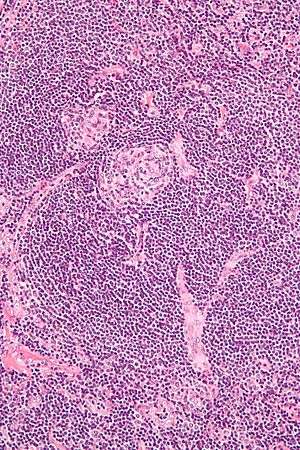

Micrograph of Castleman disease, hyaline vascular variant, exhibiting the characteristically expanded mantle zone and a radially penetrating sclerotic blood vessel ("lollipop" sign). H&E stain. | |